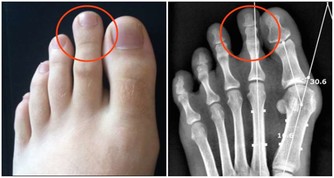

菠蘿蛋白酶是一種蛋白質消化酶,使這種熱帶水果成為最有效的抗炎食品之一。研究表明,吃菠蘿可以減輕膝關節骨性關節炎和類風濕性關節炎的疼痛,降低腕管綜合症患者的腫脹。